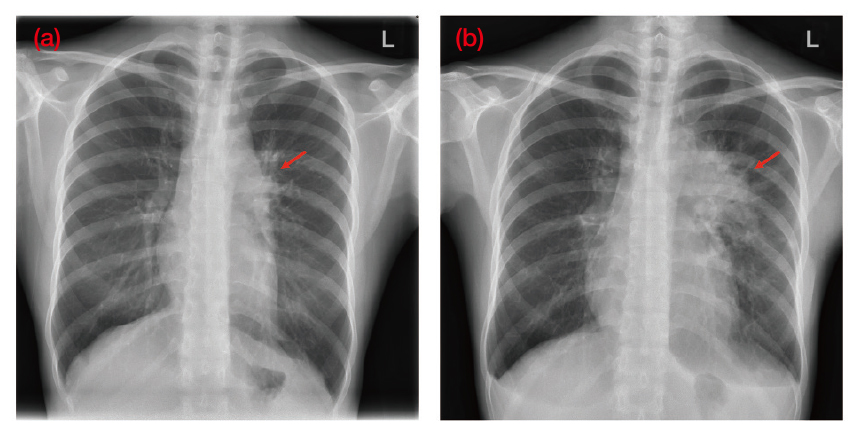

The treatment of HL has evolved considerably over the last 40 years30 and to illustrate the clinical performance of the BV+AVD chemotherapy regimen in advanced HL, Dr. Sin shared a case of a 28-year-old female who initially presented with chronic cough and dyspnea at the general outpatient clinic (GOPC). Furthermore, she was a non-smoker with no past medical or family history of cancers. Dr. Sin explained that the patient was initially treated for an upper respiratory tract infection (URTI) and despite this her symptoms did not improve. Hence, she reattended the GOPC and subsequently her treatment was escalated to an anti-asthmatic treatment, however, her symptoms persisted. Then in February 2022, patient attended the accident and emergency (A&E) and was promptly referred to the medical team for further assessment. Dr. Sin explained that it was during this admission a left-sided hilar lung mass was seen on her erect chest x-ray (Figure 3a).

Figure 3. An erect chest x-ray of the patient (a) taken during onset of symptoms at first medical consultation in early February 2022 and (b) taken prior to the commencement of chemotherapy in April 2022. Red arrows indicate (i) early signs of left hilar changes, (ii) prominent left hilar and mediastinal masses (Image provided by Dr. Sin)

After diagnosis, patient was started on 6-cycled BV+AVD treatment in April 2022 and prior to commencing the first chemotherapy session, a further chest x-ray was taken which revealed a noticeably larger lung mass indicative of rapid disease progression, according to Dr. Sin (Figure 3b).